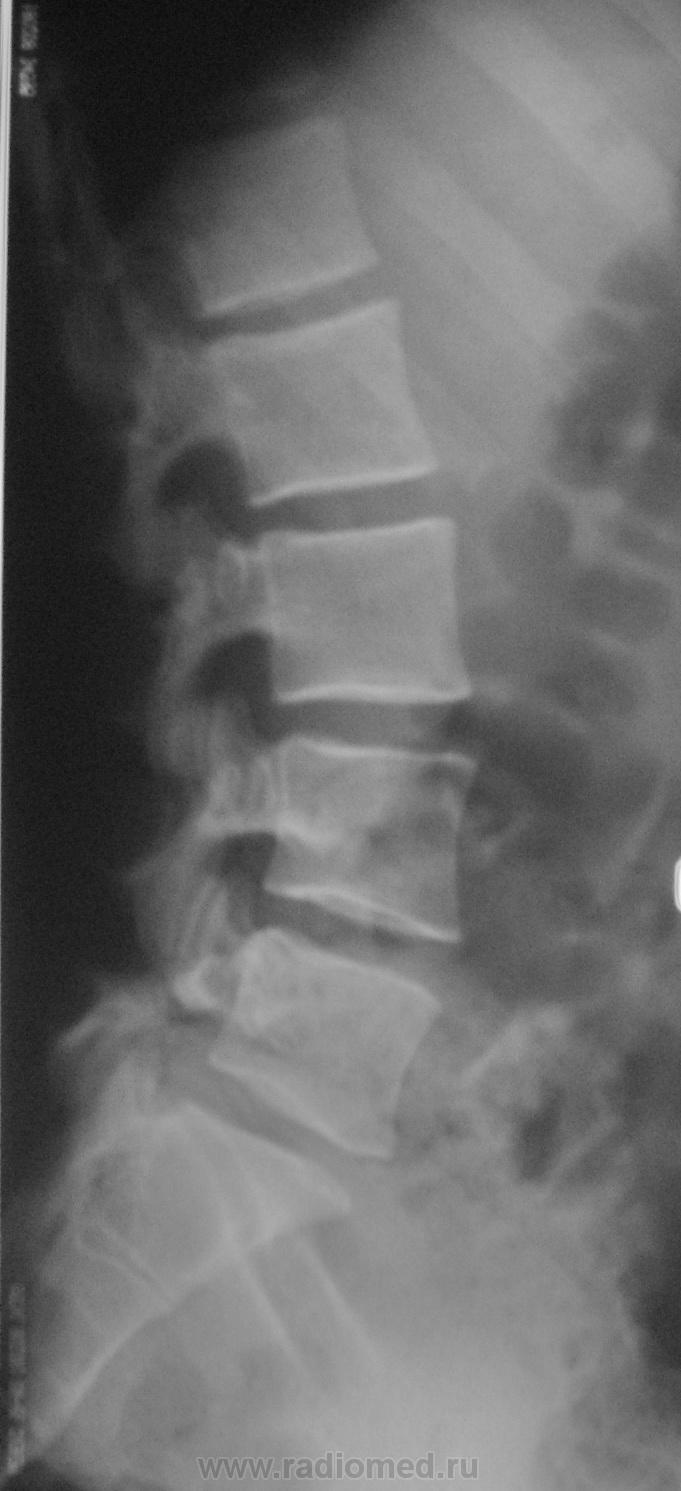

Пол пациента: Женский пол Тип патологии: Врожденная патология Область исследования: Скелетно-мышечная система Методы исследования: Rg Молодая женщина пришла на снимок поясничного отдела. Другая женщина, которая занимается рукопашным боем, обратилась с жалобами на боли в пояснице, после неудачного броска. https://radiomed.ru/sites/default/files/styles/case_slider_image/public/user/712/sl274202.jpg?itok=nrVgJub5 https://radiomed.ru/sites/default/files/styles/case_slider_image/public/user/712/sl274211.jpg?itok=ON6uvgKI https://radiomed.ru/sites/default/files/styles/case_slider_image/public/user/712/sl274212.jpg?itok=NmuMvaE1 https://radiomed.ru/sites/default/files/styles/case_slider_image/public/user/712/sl274213.jpg?itok=nP2dg6tE ID:18475 Пт, 27/01/2012 - 18:10 #1 Фаина Не на сайте Был на сайте: 2 года 11 месяцев назад Зарегистрирован: 14.12.2008 - 16:51 Публикации: 323 В первом случае, кроме остеохондроза и несросшихся апофизов, честно говоря, ничего критичного" не увидела. А во втором случае, не спондилолиз ли в L5?! Пт, 27/01/2012 - 18:17 #2 Наталия Не на сайте Был на сайте: 8 лет 7 месяцев назад Зарегистрирован: 30.07.2008 - 13:24 Публикации: 538 Во втором случае вероятнее спондилолиз. Пт, 27/01/2012 - 18:25 #3 Глазков Игорь А... Не на сайте Был на сайте: 9 месяцев 1 неделя назад Зарегистрирован: 19.12.2008 - 20:41 Публикации: 1597 Шморля в каудальной части тела позвонкаТ12 Прийди к Себе Пт, 27/01/2012 - 21:15 #4 И.Бондаренко Не на сайте Был на сайте: 3 дня 7 часов назад Зарегистрирован: 13.09.2011 - 22:55 Публикации: 9206 Случай №1. Грыжа Шморля Т12, несросшиеся апофизы L2,5 или обызвествившиеся грыжи дисков. Случай №2. Спондилолиз дужки L5. Ср, 01/02/2012 - 21:08 #5 Natalja Не на сайте Был на сайте: 13 лет 10 месяцев назад Зарегистрирован: 27.01.2012 - 22:08 Публикации: 4 Глазков Игорь Артурович wrote: Молодая женщина пришла на снимок поясничного отдела. Другая женщина, которая занимается рукопашным боем, обратилась с жалобами на боли в пояснице, после неудачного броска. В первом случае смущает L2, травмы не было? Чт, 02/02/2012 - 14:35 #6 Глазков Игорь А... Не на сайте Был на сайте: 9 месяцев 1 неделя назад Зарегистрирован: 19.12.2008 - 20:41 Публикации: 1597 травму отрицает Прийди к Себе

Случай №1. Грыжа Шморля Т12, несросшиеся апофизы L2,5 или обызвествившиеся грыжи дисков.

Шморля в каудальной части тела позвонкаТ12